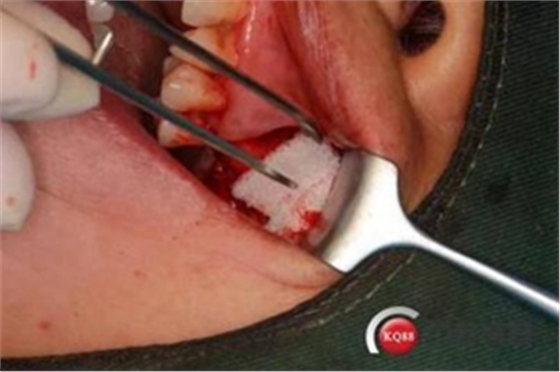

大家好,我是梁老師的助理小依。由于梁老師每天手術(shù)檔期安排較滿,加上經(jīng)常出差講課,沒有時間整理病例 。為了方便大家更及時的了解梁老師最新手術(shù)動態(tài),以后將由我為大家整理并推送梁老師最新經(jīng)典案例。案例文字旁白少,但圖片會盡量完整展示手術(shù)全過程,供大家學(xué)習(xí)參考。有任何問題,可以留言,梁老師會親自為大家解答。感謝大家對梁老師的支持和關(guān)注!